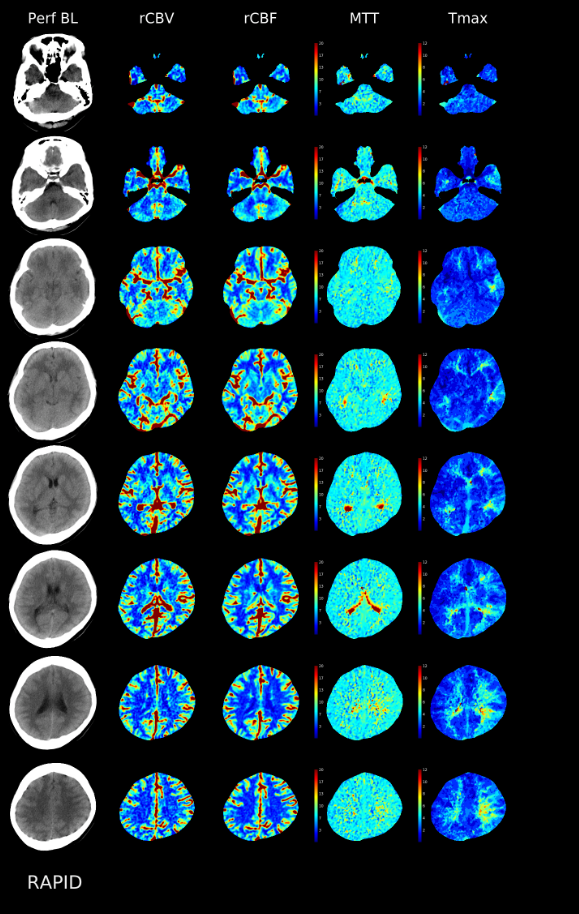

뇌 퍼퓨전 씨티인데 어떤지 봐주실 분 계실까요?

CBV, CBF, MTT, Tmax는 뭔지 혹시 설명가능할까요? ㅠㅠ 아는 의사쌤이 계시면 CD가지고 가서 설명듣고싶은데 없네요....

간단히 설명 드리면 뇌 혈류가 감소 또는 증가한 부위가 없는지 확인하는 검사입니다.

다만 올려주신 사진 상은 뇌 혈류가 감소된 부분은 없이 정상입니다.